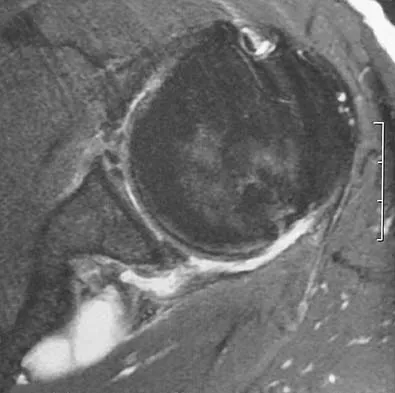

A 45-year-old man has had left thigh pain for the past 4 months. An AP radiograph, bone scan, MRI scans, and biopsy specimens are shown in Figures 6a through 6f. What is the most appropriate treatment?

Explanation